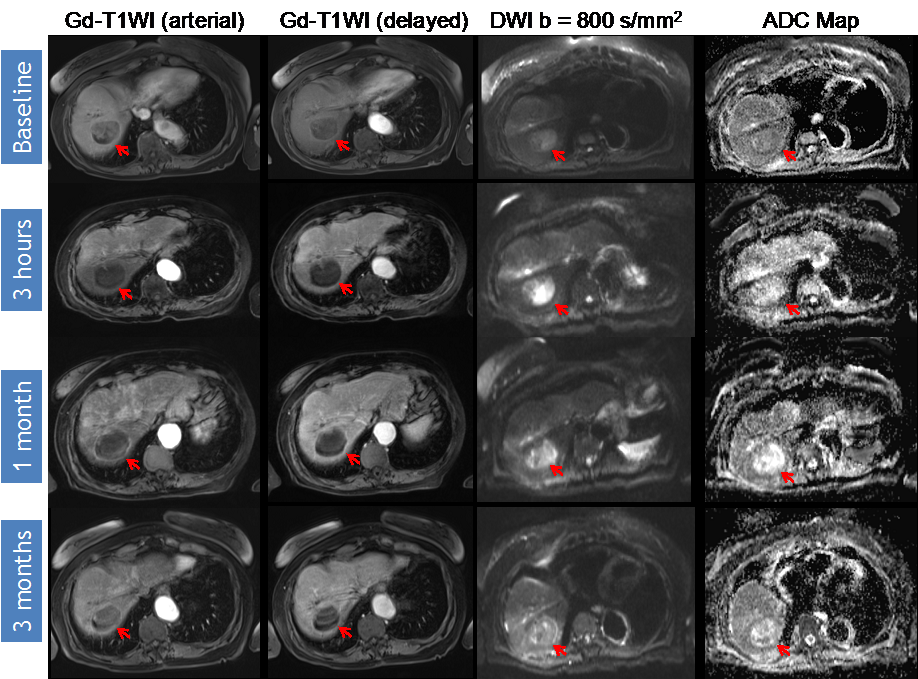

DWI Response Assessment after DEB-TACE treatment. 69-year-old man presented with a segment V HCC (arrow) without macrovascular invasion or extrahepatic disease. Note that there is decreased peripheral enhancement at 3 h that becomes more evident at one month. When analyzing DWI images, ADC values increased ≥20% in the treated region (baseline ADC 0.704 × 10−3 mm2/s, post-3 h ADC 1.30 × 10−3 mm2/s); however, a small nodule of restricted diffusion persists at one month (ADC 0.940 × 10−3 mm2/s). The findings represent a subjective and objective measurement of response, in this case representing partial response (PR) to therapy.

Identifying early disease progression or absence of response to locoregional therapies is imperative and allows for individualized therapeutic strategies and potentially improved overall prognosis in patients. Volumetric ADC changes after conventional TACE (cTACE) have been investigated at one month after therapy and correlated with six-month RECIST and mRECIST objective responses [27]. Increases in volumetric ADC values to 1.6 × 10−3 mm2/s in at least >39.8% of the tumor volume correlates with objective response by mRECIST at six months with a sensitivity of 88.4% and specificity of 78.6% (p = 0.001). Similar results were obtained by using RECIST response criteria, albeit with lower sensitivity and specificity [27]. An absolute increase in ADC values has also been observed in responding lesions compared to non-responders by mRECIST criteria for cTACE [28]. Kokabi et al. [29] demonstrated a % ADC increase for responders vs. non-responders (36.4% vs. 7.4%; p < 0.001) 3 h after DEB-TACE intervention, which further increased after one and three months (98.1% and 115.2%) for responders, whereas no relevant increase for non-responders (−0.1% and 2.1%, p > 0.05) was evident. Exemplary diffusion-weighted imaging cases from this study with complete response (Figure 1), partial response (Figure 2), and progressive disease (Figure 3) are illustrated below. A significant percent increase in ADC values has also been reported by another study in responding lesions one and three months post-DEB-TACE compared to non-responders by mRECIST and EASL criteria [30].

Variable timelines in terms of changes in DWI were reported with some studies demonstrating significant changes in treated lesions within 24 h [29,43,46], 2–3 days [10] or 5–7 days [45] after therapy, all of which could predict the outcome. However, another study only detected a significant ADC change following 1–2 weeks after treatment but not before or after that time period [47]. Kokabi et al. [29] demonstrated a continuous increase of obtained ADC values during the course of three months for objective treatment responders but not for non-responders after DEB-TACE (Figure 1, Figure 2 and Figure 3). Chung et al. [46] investigated intraprocedural DWI changes following cTACE and did not detect a significant % ADC change (3%; SD: ±16.4%) in treated lesions. However, an intraprocedural relative ADC value increase or decrease of ≥15% of individual lesions was associated with a 100% positive predictive value, a specificity of 100%, and a sensitivity of 46% for tumor response after 1 month (EASL) following cTACE.